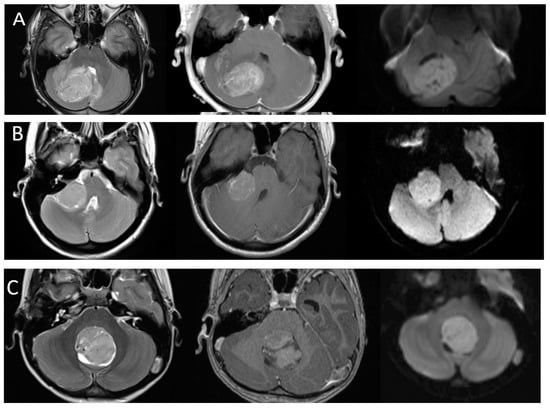

As the understanding of the importance of molecular and genetic profiles of these tumors increases, there has been growing interest in identifying imaging characteristics specific to the different molecular subtypes and some distinguishing features have emerged (Figure 3). Non-WNT/non-SHH tumors are the most common and are classically located in the midline, involving the fourth ventricle. Of the subgroups of non-WNT/non-SHH, group 3 tumors tend to show robust enhancement while group 4 tumors have been reported to be hypoenhancing [37]. In contrast to most medulloblastomas, group 3 tumors are often reported to have ill-defined margins [35]. WNT tumors are the least common, but have the best prognosis, and can arise near the cerebellopontine angle or in the midline. SHH tumors have intermediate prognosis, are associated with desmoplastic pathology, and are often located laterally in the cerebellar hemispheres [38]. It is important to note that while suggestive, location and imaging characteristics are not yet absolute predictors of tumor type. Machine learning approaches such as radiomics and multi-parameter imaging including MR spectroscopy have shown promise in teasing out molecular subgroups by imaging [39,40,41,42].

Figure 3.

Imaging appearances of molecular subtypes of medulloblastoma. Each row includes axial T2-weighted, axial post-contrast T1-weighted and axial diffusion-weighted images from left to right. (Row (A)): SHH. Imaging demonstrates an off-midline lesion with the classic cerebellar hemispheric location of these lesions. (Row (B)): WNT. Imaging demonstrates the classic CP angle location of this subtype, although many of these lesions may arise in the midline as well. (Row (C)): Group 3 and (Row (D)): Group 4. These tumors are classically located in the midline. Note the relative hypoenhancement of the group 4 tumor, which has been a described feature. All lesions demonstrate characteristic restricted diffusion.